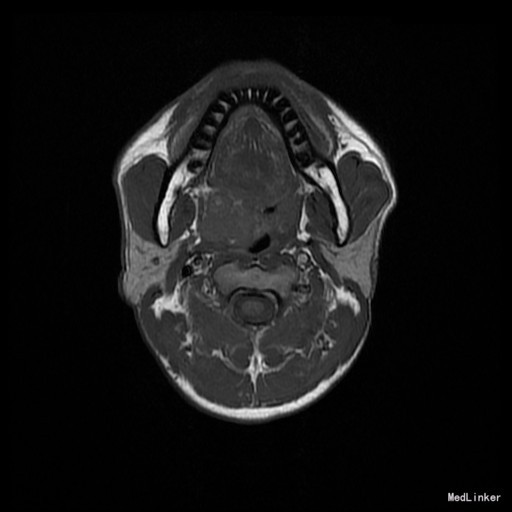

患者:男,42岁 主诉:发现右侧软腭肿物7年余。 病史:患者诉7年余前发现右侧软腭肿物,渐进性增大,无咽痛邓特殊不适。

查体:右侧软腭至硬腭处见一肿物,约5*3cm,质硬,固定,边界欠清,表面粘膜光滑。 辅助检查:外院颌面CT提示:右侧软腭实性占位,并累及鼻咽、口咽壁,建议MRI增强检查。

入院诊断:咽旁肿物(右侧软腭肿物性质待查) 治疗:入院后咽部MRI示:软腭右部软组织肿块,性质待定,鼻咽腔及口咽腔明显变窄。,未见手术禁忌,遂于全麻下行“右侧咽旁间隙肿物切除术”,术程顺利,术后未见并发症。病理:多形性腺瘤。